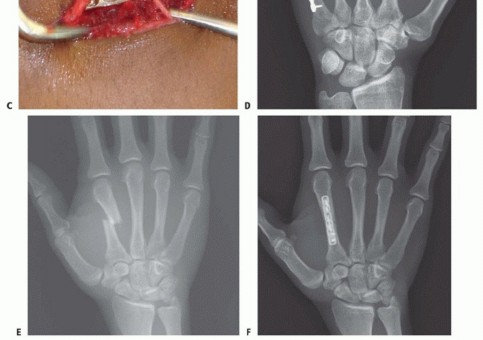

TECH FIG 6 • A,B. Intra-articular head fracture of the fourth metacarpal. C. Dorsal approach to an MP joint. Extensor tendon beneath top retractor. Capsule grabbed by pickup forceps. Articular cartilage seen deep to capsule. D,E. Intra-articular fracture stabilized with headless screws. (continued)

TECH FIG 6 • (continued) F,G. Intra-articular head fracture stabilized with extra-articular screws.

TECH FIG 7 • A,B. Coronal intra-articular fracture that extends to the metacarpal neck. C,D. If there is no comminution, the fracture can be addressed through a volar approach and stabilized with lag screws.